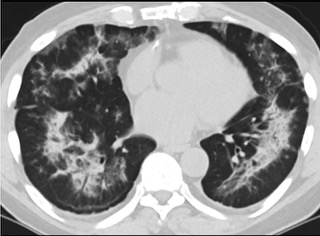

6天后的轴向CT平扫图像显示毛玻璃影变为实变和轻度结构扭曲。(同一病人CT影像)

16位被文献报道为电子烟肺炎的患者被专家判定为“病毒性感染”,即有可能是新冠肺炎的“疑诊患者”,其中更有5位临床症状和治疗情况相对完整的患者被判定为“中度可疑”。因此在2019年美国报道的电子烟肺炎中存在病毒性感染的病例,而且不排除美国电子烟肺炎中存在新冠肺炎的可能性。